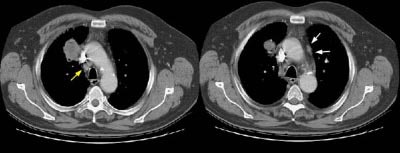

Example 2: This patient with non-small cell lung cancer demonstrates many findings which are suspicious for mediastinal invasion. There is greater than 3 cm of contact between the mass and the mediastinum, loss of the mediastinal fat plane between the mass and the left pulmonary artery, deformity of the left pulmonary artery, and pericardial thickening (yellow arrows). The patient also demonstrates contralateral mediastinal adenopathy (N3 nodes -- white arrow), subcarinal adenopathy (SC), and bilateral pleural effusions.

NOTE: Click image to enlarge